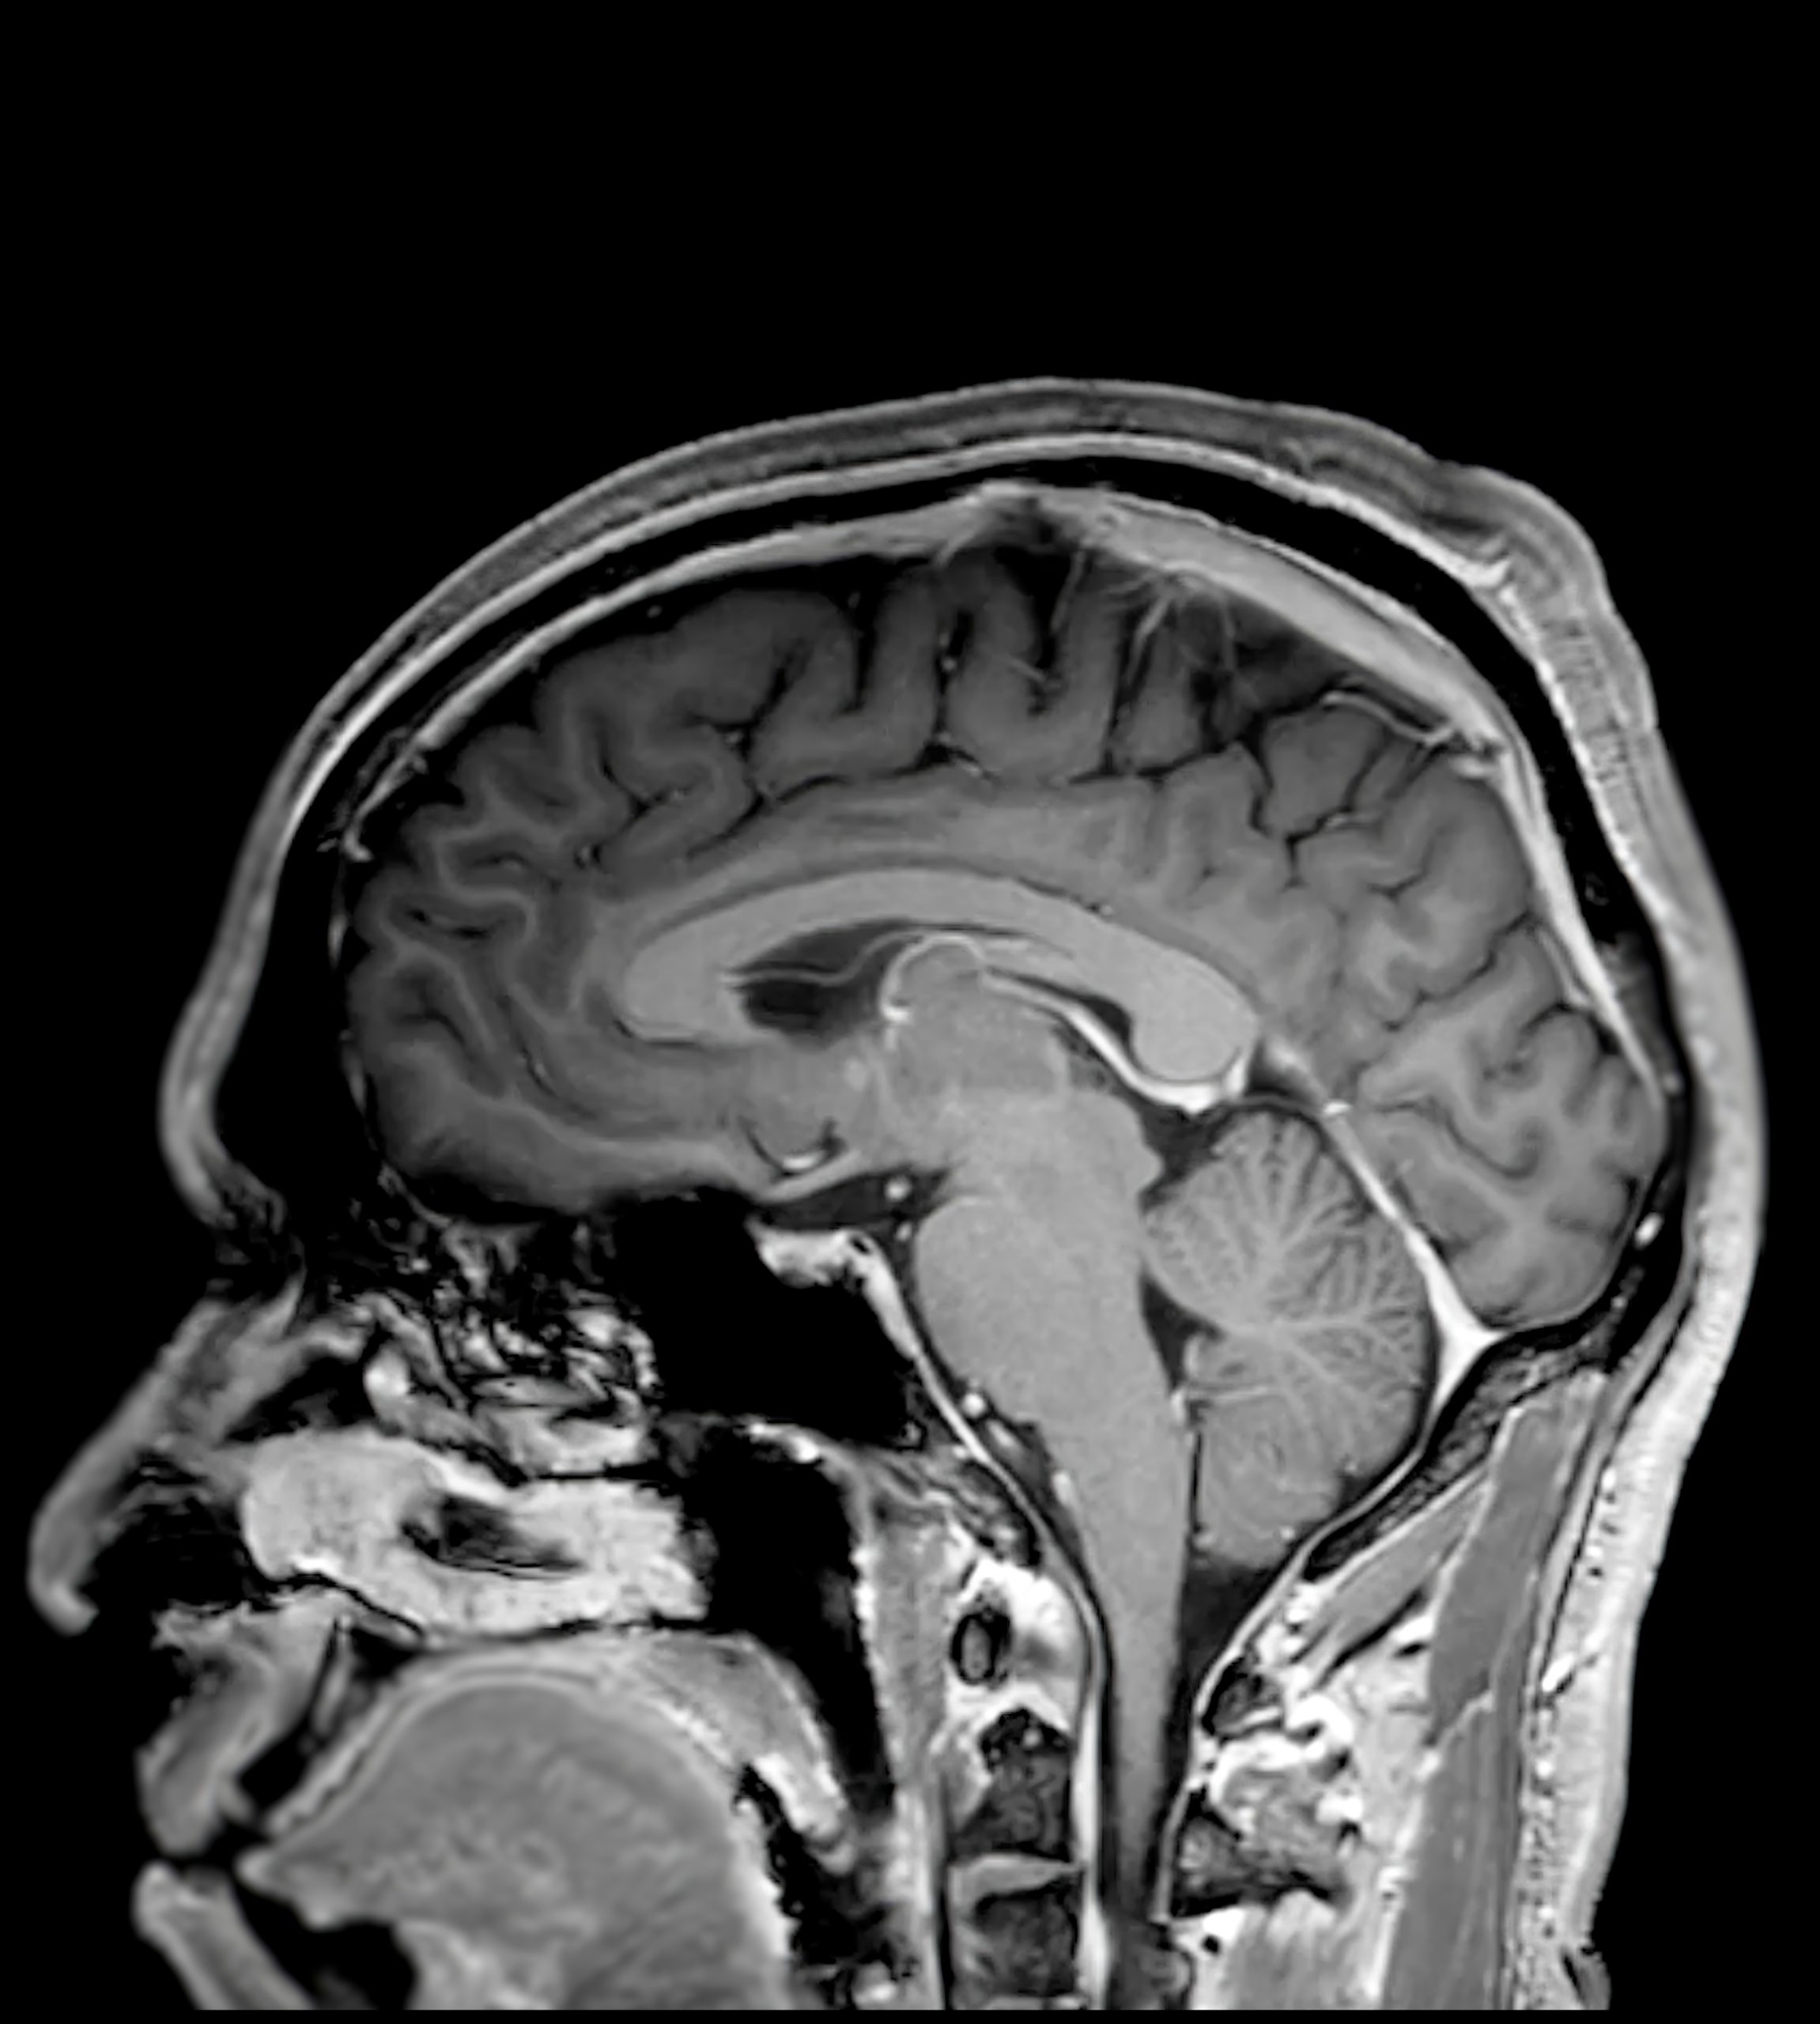

A Full Body MRI Scan is one of the most powerful tools in modern preventative medicine — offering a comprehensive, radiation-free assessment of your internal health. Unlike traditional imaging, MRI uses magnetic fields and radio waves to create highly detailed images of your organs, tissues, joints, and blood vessels, helping to identify early changes long before symptoms develop.

This advanced scan provides exceptional clarity across the brain, spine, chest, abdomen, and pelvis, detecting potential concerns such as tumours, cysts, vascular disease, inflammation, or organ abnormalities at their earliest and most treatable stage. It is particularly valuable for uncovering silent conditions that may go unnoticed during routine health checks.

The MRI is conducted with our partner facility. The scan is quick, safe, and non-invasive, using magnetic resonance technology to capture images. This means that MRI scans have no damaging radiation to the body, unlike CT Scans. The process typically takes 30–50 minutes, with no special preparation required.